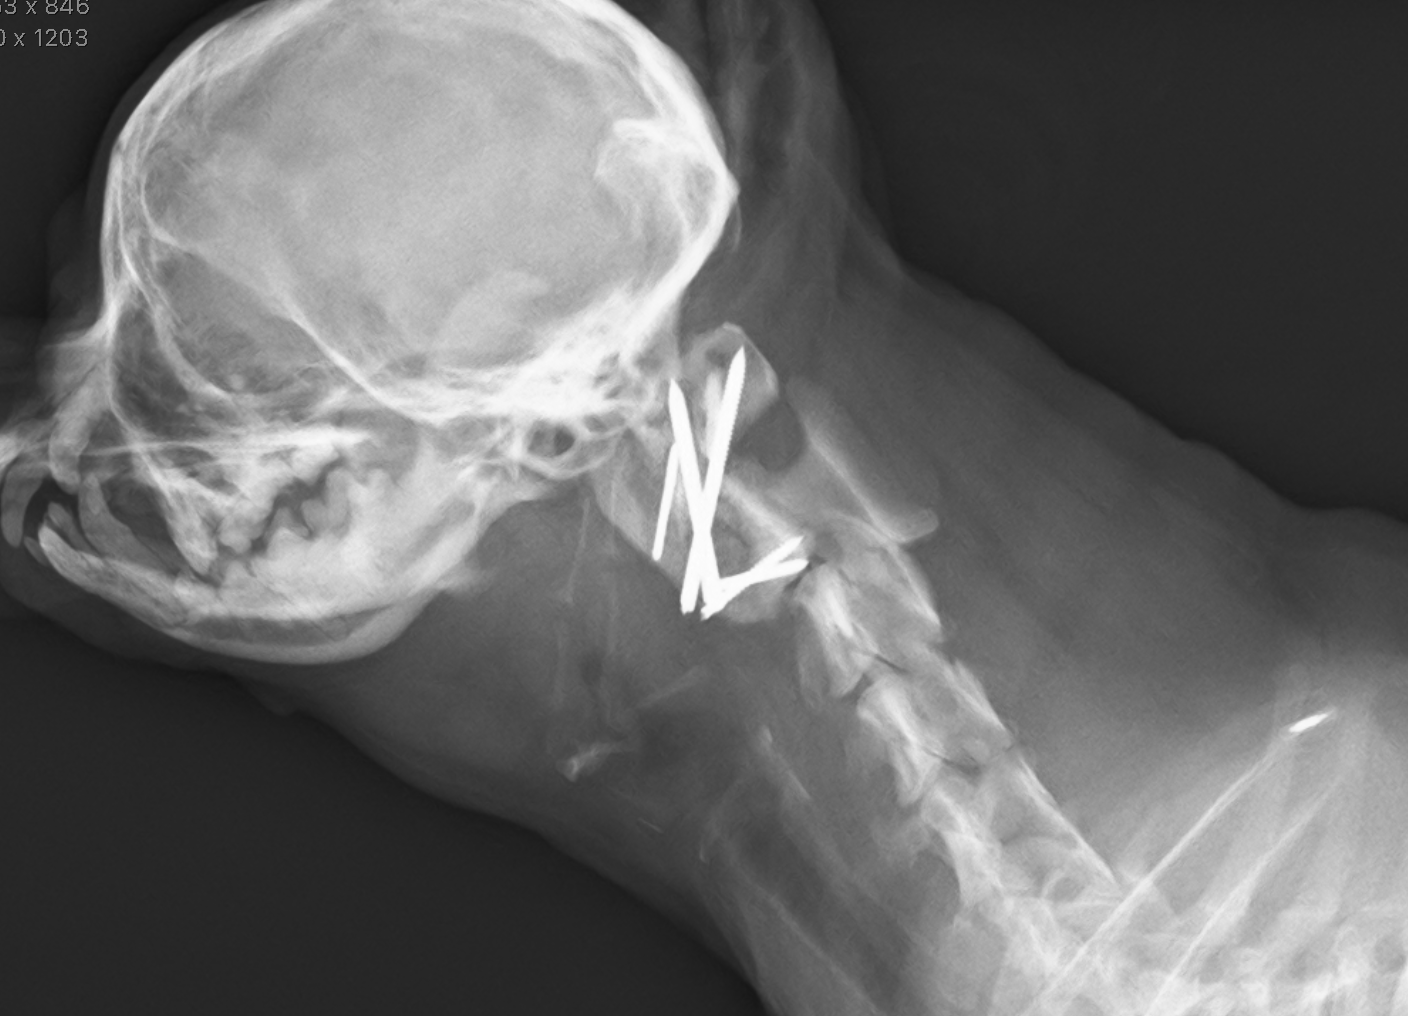

CTより軸椎歯突起の背側変移、MRIよりC1-2領域に脳脊髄液の貯留が認められた

腹側椎体固定術

after